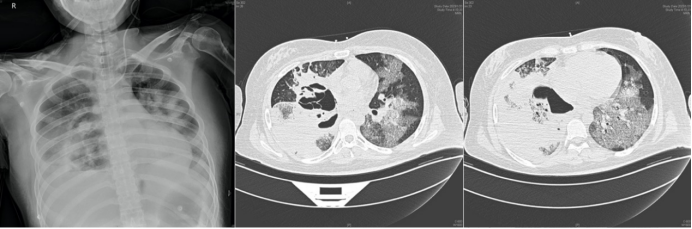

病例8:男性,51岁,主诉“反复咳嗽、咳痰4月余,间断发热1个月”于2021年12月27日入院。4个月前患者因急性淋巴细胞白血病就诊于某三甲医院行VICLD方案化疗,化疗期间出现咳嗽、咳痰伴间断发热,诊断为肺部感染。胸部CT提示肺部感染,查痰NGS提示小孢根霉;痰培养结果为耐碳青霉烯类鲍曼不动杆菌(CRAB),予抗感染及小剂量激素治疗后体温正常,咳嗽、咳痰好转。既往史:患者于2020年6月确诊为急性B淋巴细胞白血病,2020年7-9月分别行VDLD、CLEA、HD-MTX/VL化疗3次,2021年7月白血病复发。2021年12月28日入院后胸部CT示:左下肺病变严重,增强CT检查在此发挥重要作用,可辅助评估病灶出血风险及制定规避出血的策略。支气管镜检查(图15)及组织病理学(图16)均提示毛霉感染,mNGS进一步明确诊断。由于患者血小板水平极低,一般状况差,无法耐受外科手术,遂采用支气管镜介入清创术(图17)。术中取出的由大量毛霉菌丝杂乱缠绕形成的特殊病变组织,被笔者命名为"毛霉菌丝体(mucormycelium)"(图18)。经规范治疗一个半月后,患者实现彻底治愈。

图片

15  病例8气管镜检查